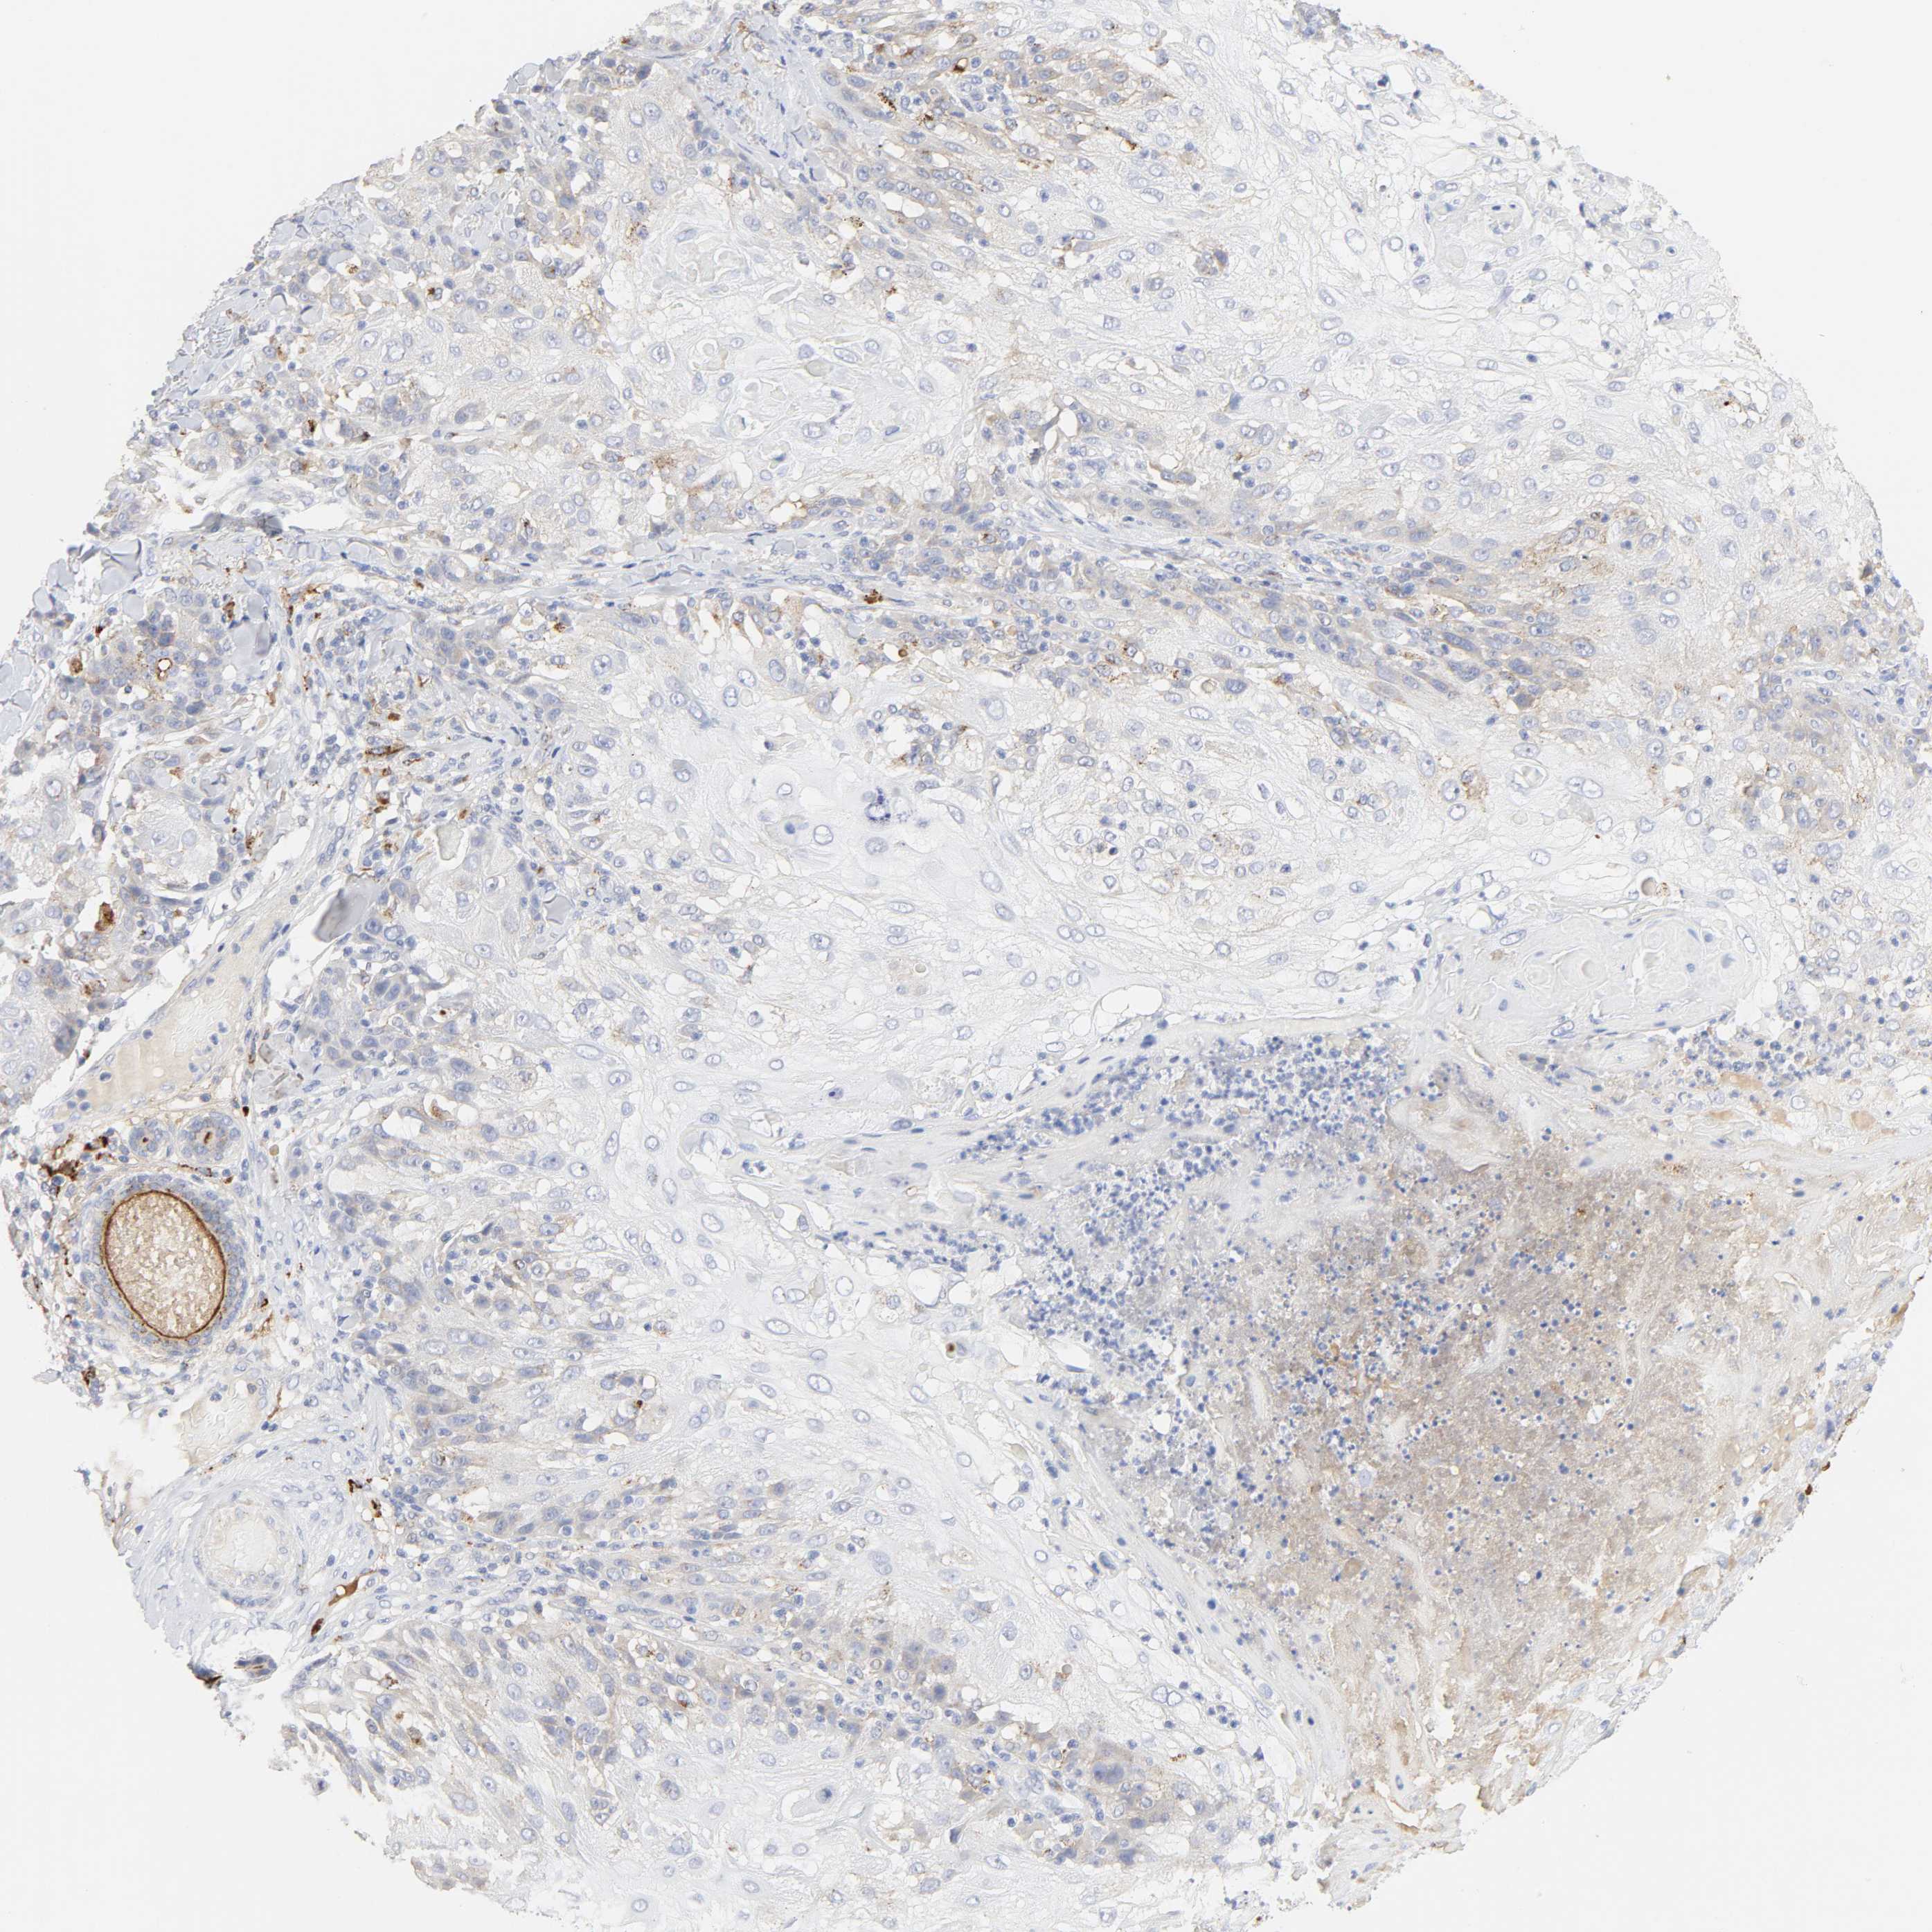

SKIN CANCER - Protein expressioni

A mouse-over function shows sample information and annotation data. Click on an image to view it in a full screen mode. Samples can be filtered based on level of antibody staining by selecting one or several of the following categories: high, medium, low and not detected. The assay and annotation is described here.

Antibody stainingi

Antibody staining in the annotated cell types in the current human tissue is reported as not detected, low, medium, or high, based on conventional immunohistochemistry profiling in selected tissues. This score is based on the combination of the staining intensity and fraction of stained cells.

Each image is clickable and will lead to virtual microscopy that enables deeper exploration of all samples and also displays staining intensity scores, fraction scores and subcellular localization as well as patient and tissue information for each sample.

Antibody HPA003756

Staining

High

Medium

Low

Not detected

Intensity

Strong

Moderate

Weak

Negative

Quantity

>75%

75%-25%

<25%

None

Location

Nuclear

Cytoplasmic/membranous

Cytoplasmic/membranous,nuclear

Squamous cell carcinoma, NOS